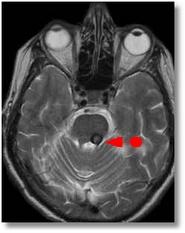

![]() |

| Cavernoma de Tronco |